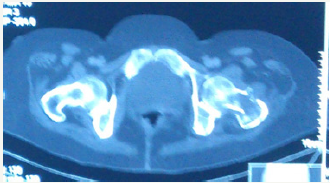

Figure 6: CT showing the pathological fracture with the lesion.

Figure 7: CT skull showing no involvement of the extracalvarial or intracalvarial structures.

A 58 year old female presented with pain in the left thigh and pelvis. She was originally radiographed (Figure 1 & 2) and was managed conservatively in the periphery. The radiographed of the skull showed no involvement of skull bones (Figure 3).Then the MRI of the femur and pelvis was done which reported it is as a cystic lesion and was advised extended curettage (Figure 4 & 5). No treatment was done. Two months after this the patient presented to us with greater pain and a pathological fracture left trochanteric region. The patient also had palpable subcutaneous masses in the head. We reviewed the MRI and did CECT pelvis and CECT head. CECT pelvis showed lytic expansile destruction of both the sacral ala with soft tissue masses extending into spinal canal causing compression of the cal sac in addition to the original lesion in the neck and trochanteric region with fracture (Figure 6). CECT head showed multiple lytic areas with formation of soft tissue masses in extra-calvirial and intra cranial locations (Figure 7). The brain parenchyma was normal. We did biopsy of the trochanteric region and nodule from scalp. Both the reports showed large tumour cells having round, irregular cleaved nuclei with 1-2 prominent nucleoli and moderate amount of cell cytoplasm with frequent mitotic figures (Figure 8). On immunohistochemistry were positive for LCA and CD-20 suggesting diffuse large B- cell lymphoma (Figure 9). The patient was then started on CHOP regime.